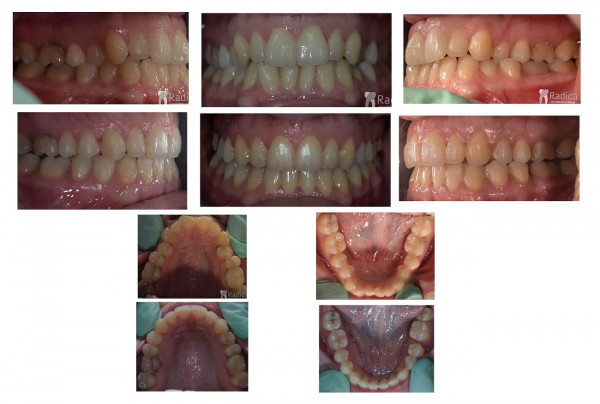

U galeriji slika su prikazani klinički slučajevi ovakvih odraslih pacijenta bilo da se radi samo o ortodontskoj terapiji ili predprotetskoj ortodonciji.

Kompresija –fiksni aparat bez ekstrakcije zuba

Slučaj 2